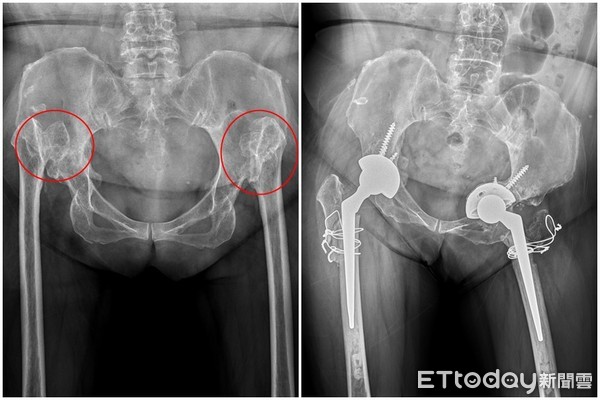

▲先天性髖臼發育不全,從小走路容易單測脫臼跛行。 (圖/亞大醫院提供)

台中59歲周阿姨年輕時走路經常感到雙腿無力、搖搖晃晃,造成腰部、鼠蹊、膝蓋不適,雖因不影響生活,但總被笑說「像素還真走路」。直到去年雙腿開始疼痛,導致無法久走,更影響工作表現,赴醫檢查確診為兩側先天性髖臼發育不全,併嚴重髖關節炎,經兩側人工全髖關節置換手術治療後,症狀終大幅緩解。

唐國民介紹,先天性髖臼發育不全是因患者於嬰幼兒時期髖臼發育不正常,導致髖關節解剖位置結構性異常,通常嬰兒出生三個月內,可透過全身檢查、超音波檢查等方式發現問題,而開始走路的孩子,可觀察其是否跛行(單側脫臼),或走路如鴨子一般搖晃(雙側脫臼)而提早發現症狀。

唐國民指出,若患有先天性髖臼發育不全的民眾,未能在早期接受治療,成年後容易造成嚴重的髖關節炎,需接受人工全髖關節置換手術,就得切除損壞的關節和股骨頭,再安裝人工髖關節,雖然隨著醫療科技的進步,患者術後恢復快,但此種手術困難度較高,仍需有經驗的醫師執行,以達較佳的預後。